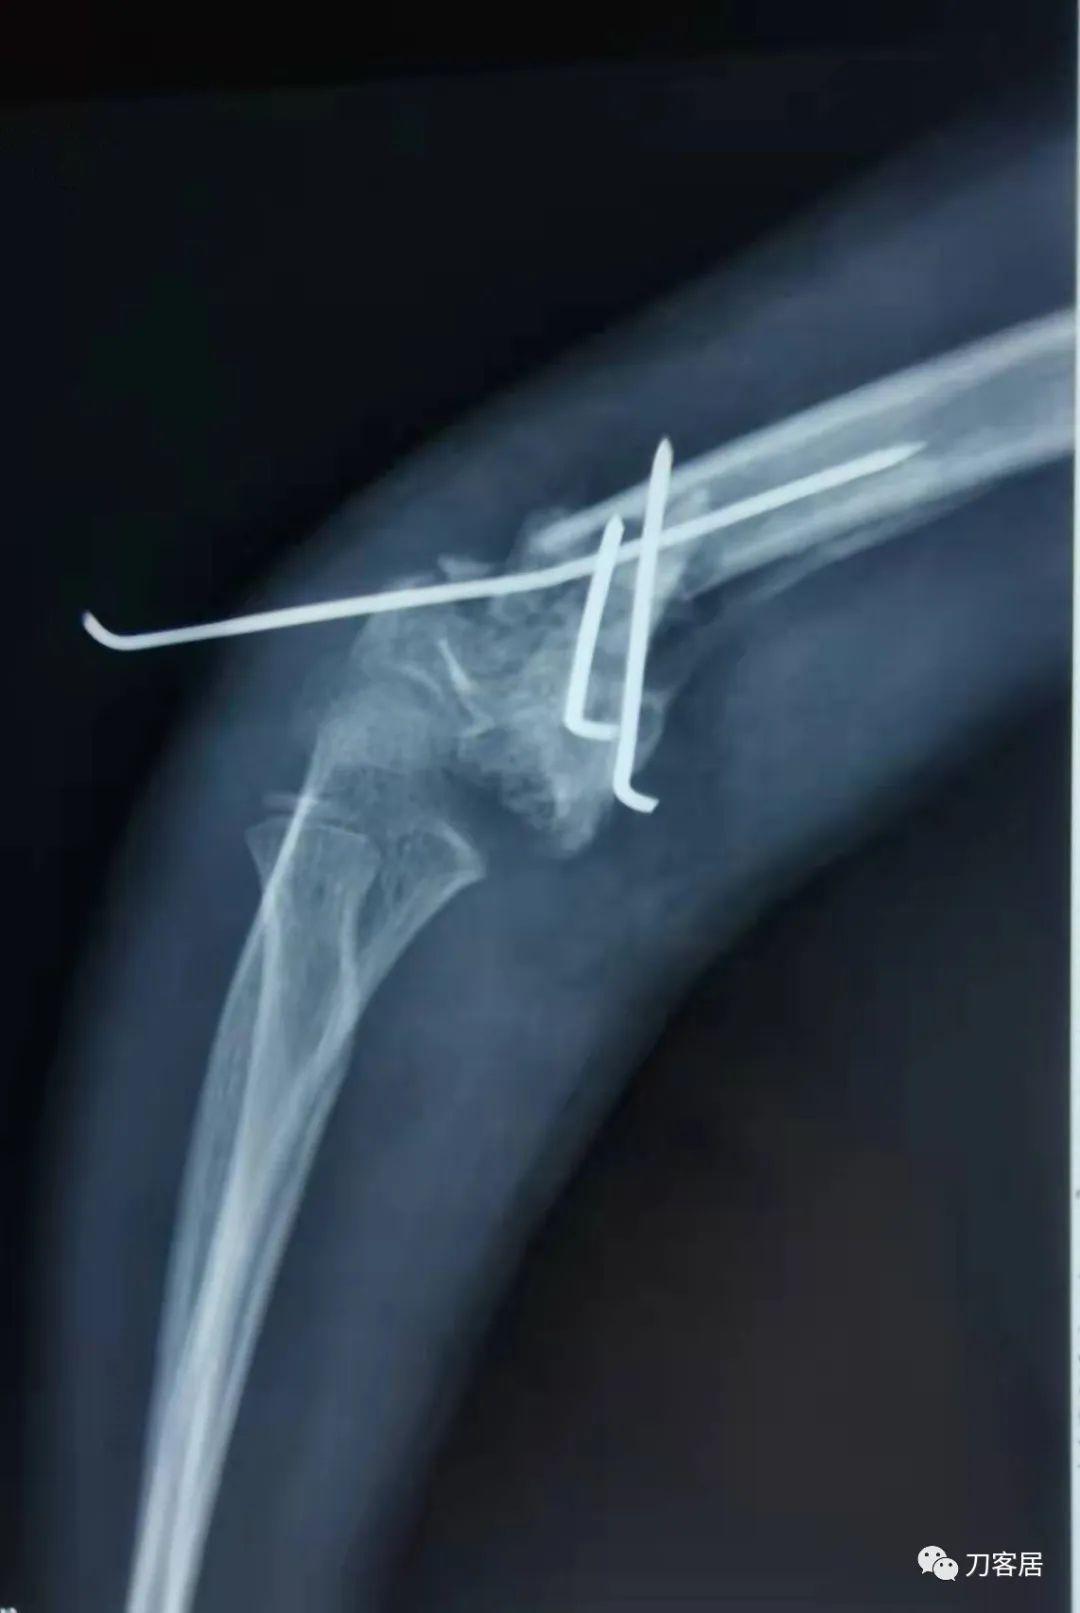

诊疗经过:2021年9月23日在全麻下行左肱骨髁间粉碎性骨折切开复位内固定术,术后予以抗感染、消肿止痛等对症治疗。

患者术后病情平稳,拍片复查示骨折对位对线良好,内固定在位。外固定稳妥。于2021年9月29日出院。

当地省中医院术后正位X线片

当地省中医院术后侧位X线片